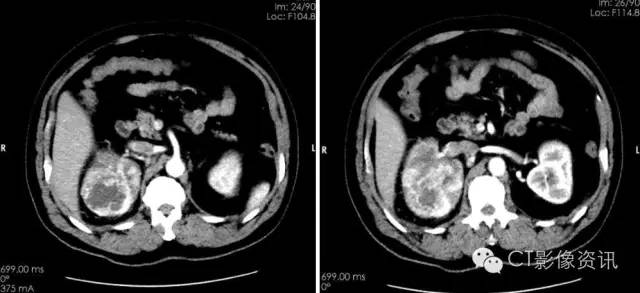

分泌期及排泄期可见病灶不均匀强化,对比与周围明显强化的肾脏组织,病灶边界清晰,实质内有不规则低密度坏死区。